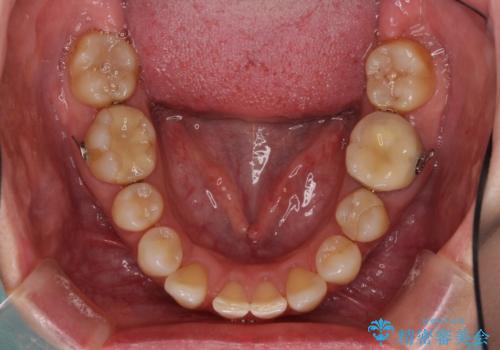

③上顎左右第一小臼歯2本を抜歯し、下顎はスペースを閉じる

いずれもワイヤー矯正が望ましい治療方法ですが、家が遠方であり、近い将来出産される予定もあるとのことで、何とかマウスピース矯正でも対応可能な③にて治療を行うこととしました。

マウスピースでの抜歯矯正特有の抜歯スペースに向かって奥歯が傾斜する動きが顕著に表れ、ディープバイトは改善されませんでした。

前歯のみが強く接触し、奥歯で咬めない期間も続いたため、ワイヤー装置などを補助的に使用し、何とか終了させることができました。